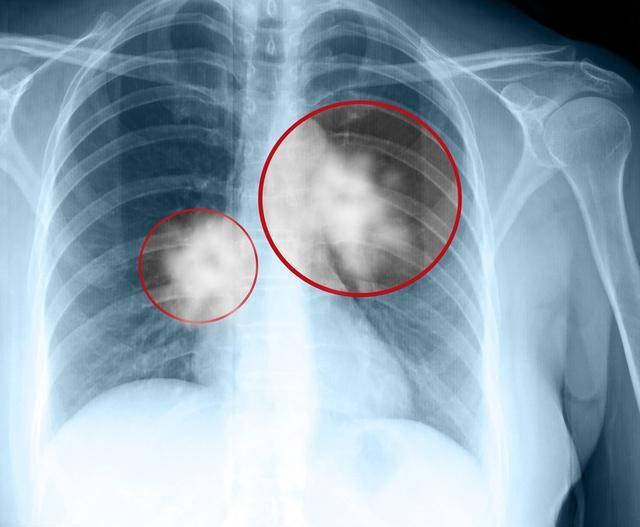

肺癌消融术常见适应症:1.患者拒绝手术;2.心肺功能差或合并全身其他疾病,不能耐受手术;3.肿瘤位置特殊,无法手术治疗;4.肿瘤术后复发或者放化疗后肿瘤进展; 5.手术探查的补救;6.减瘤综合治疗或姑息治疗缓解症状。由此可见,消融治疗肺癌的适应症非常广泛,在肺癌早期、中期、晚期都可以使用。

对于早期肺癌,从消融适应症也可以看出,是用于拒绝手术和无法耐受手术者。手术治疗在早期肺癌中的地位是无法撼动的,不可替代的。一般来说只有手术治疗才能让早期肺癌达到根治效果。所以手术是肺癌首选和最主要的治疗方法,所有早期肺癌病人,建议先做肺功能等检测,若肺功能不能达到手术标准,再考虑射频消融或其他方案。射频消融术对于肺内病变是局部控制,射频消融治疗时消融区需从病变区延伸至正常组织 0.5~1cm范围才能达到完全毁损,所以如果范围达不到,可能会出现肿瘤细胞残留。如果范围过大,肺部及周围组织较薄弱,容易造成周边损伤,引起气胸、胸腔积液、胸痛等并发症。射频消融不是一次性,由于肿瘤本身的因素或者病人身体的因素,第一次做完三个月以后还可以进行第二次消融治疗,把那些可能残存的肿瘤组织进一步消融。

肺部消融治疗近几年发展较快,让许多高龄、心肺功能差、无法行根治手术的病人得到较好的治疗效果,对于不能接受手术治疗的早期非小细胞肺癌患者,有研究表明经消融治疗的1年、3年和5年的生存率分别达到97.7%、 72.9%和55.7%。但是对于极早期非小细胞肺癌,比如原位癌和微浸润癌,外科切除才是治愈的主要手段。目前一般采用胸腔镜下(VAST)微创手术治疗。